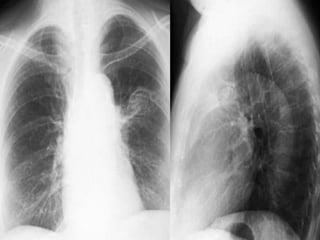

Consolidation / Lingula

Density in left lower lung field

Loss of left heart silhouette

Diaphragmatic silhouette intact

No shift of mediastinum

Blunting of costophrenic angle

Lateral

Lobar density

Oblique fissure not

significantly shifted

Air bronchogram